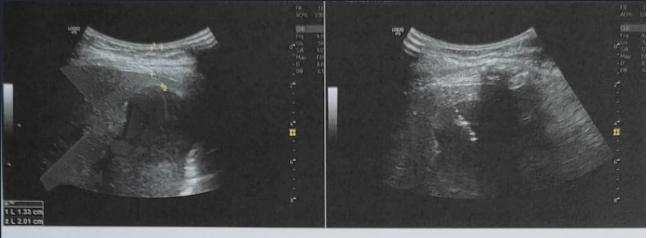

L.R.S., masculino, 8 meses, nascido a termo, com diagnóstico pré-natal de atresia de esôfago com fístula traqueoesofágica distal (Vogt IIIb/Gross C), submetido à correção cirúrgica no 3º dia de vida. Aos 3 meses, passou a apresentar episódios recorrentes de tosse durante a alimentação, engasgos, regurgitação e perda de peso progressiva. A mãe relatou dificuldade em introduzir alimentos sólidos e episódios recorrentes de infecção respiratória nos últimos dois meses. Solicitada endoscopia digestiva alta, que evidenciou estenose puntiforme da anastomose esofágica. Iniciada terapia endoscópica com dilatação esofágica utilizando vela de Savary-Gilliard. Foram realizadas 4 sessões com intervalo de 2 semanas, com melhora progressiva da aceitação alimentar e ganho ponderal adequado. Após a 4ª dilatação, o paciente encontra-se em boa evolução clínica, com alimentação por via oral plena, sem episódios de engasgos ou perda ponderal.

A estenose da anastomose ocorre, na maioria dos casos, no primeiro ano de idade, sendo a maioria diagnosticada nos primeiros 6 meses, com pico de incidência entre o 1º e o 3º mês pós-operatório [10,11]. Vários fatores são descritos atualmente na contribuição do seu aparecimento, como o fio de sutura utilizado na cirurgia, o grau de tensão na anastomose, a presença de fístula pós operatória e o refluxo gastroesofágico [10,11].

O diagnóstico deve ser suspeitado diante de sinais e sintomas como perda ponderal, disfagia, engasgos e infecções respiratórias recorrentes, vindo a ser confirmado através da endoscopia digestiva alta [11].